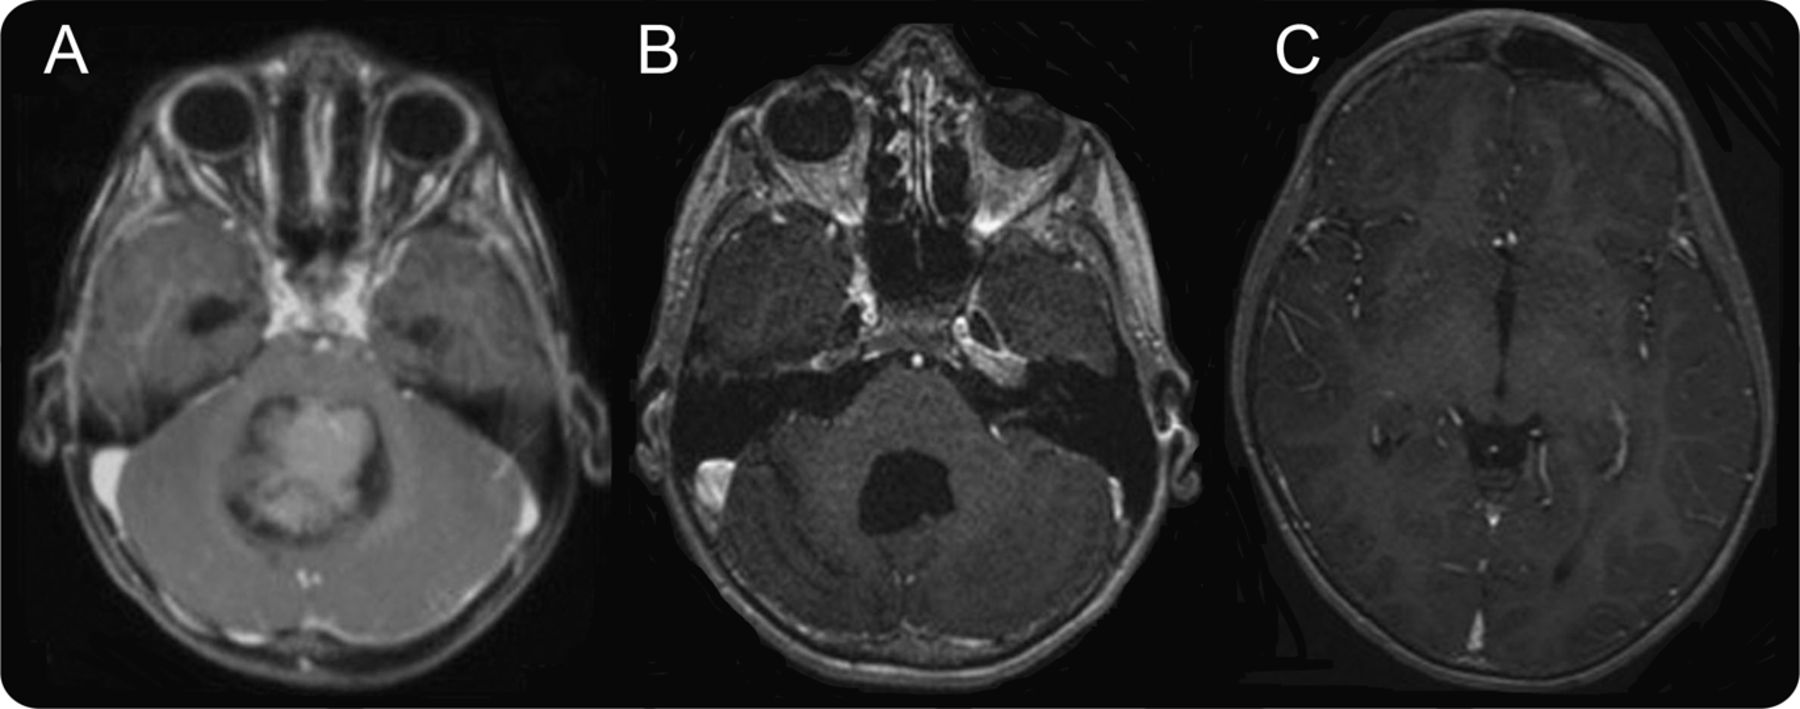

一个5岁的男孩动手术nonmetastatic第四脑室的成神经管细胞瘤(图1)。化疗和bifractionated craniospinal放射治疗管理。四年后,t1加权磁共振成像对比异常血管在右大脑侧裂透露,在随访期间逐渐增加;血管造影证实的动静脉畸形(AVM) (图2)。即使它是无症状的,其位置和增长促使我们治疗(栓塞然后残留病灶的切除)。这非常罕见的情况下辐射诱导AVM表明,当异常血管成像发生在后续1,2与血管造影进一步调查是必要的,考虑进一步治疗。